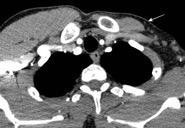

Carcinoma subglótico

Tumor poco frecuente. 1,8% de los tumores laríngeos.

Tendencia a invadir el anillo cricoideo y el esófago.

Ganglios + frecuentes

Mac Neill SD et al. Survival of patients with subglottic squamous cell carcinoma. Curr Oncol. 2018